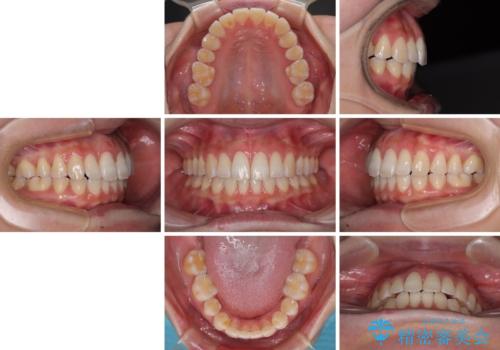

下顎前歯の欠損歯列 ワイヤー装置での矯正治療

- 下顎前歯の欠損により隙間ができていることを気にして来院された患者様です。

下顎前歯が2歯欠損しており、スペースになっており、上顎は叢生歯列となってしました。

当初は上記計画でしたが、レントゲン撮影よりインプラント埋入は困難と判断され、患者様と相談の上、歯を削ってブリッジとするよりも、奥歯の咬み合わせを多少妥協することとなっても、スペースを閉じて仕上げていくこととしました。

1年弱で治療方針を変更したため、治療期間は長くなりましたが、スペースは無事に閉じ、咬合の違和感なく仕上げることができました。

ただし、両方の臼歯部は理想的な咬合とは言えないため、咬合による歯の外傷を防ぐため、就寝時にはマウスピースを継続使用するようお願いしております。